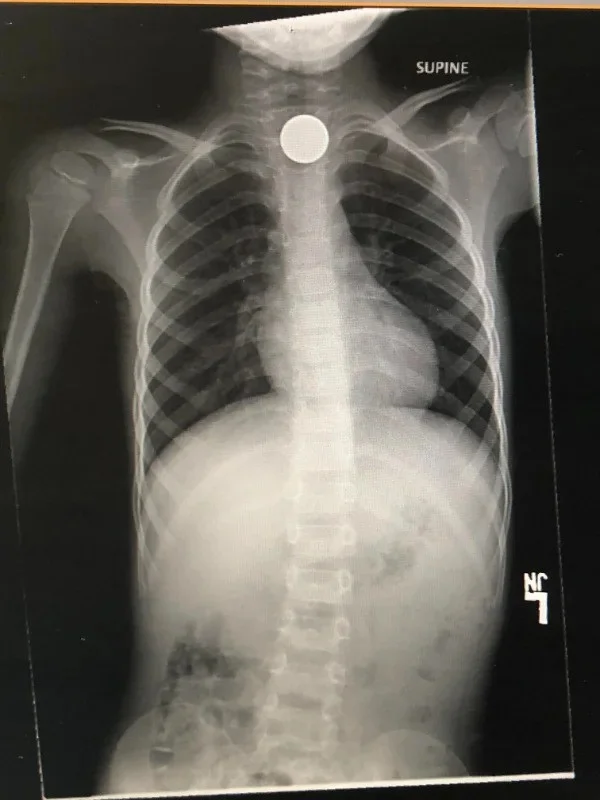

13. "Сын решил проглотить монетку и превратил пять центов в 4 400 долларов"